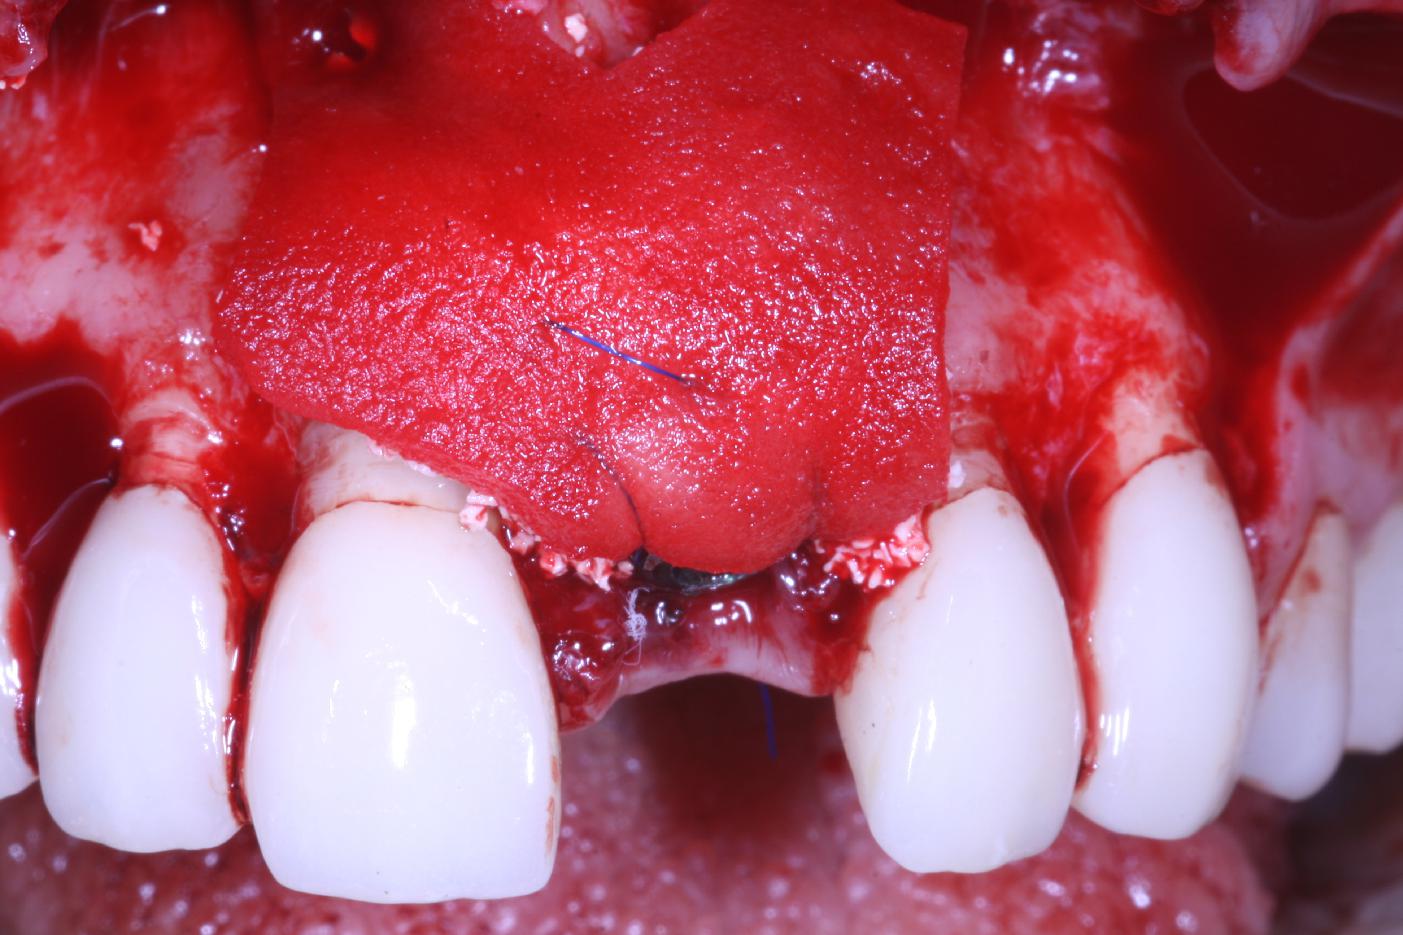

Bone defect in area 11-21 due to two lost implants (periimplantitis) after 15 years of function